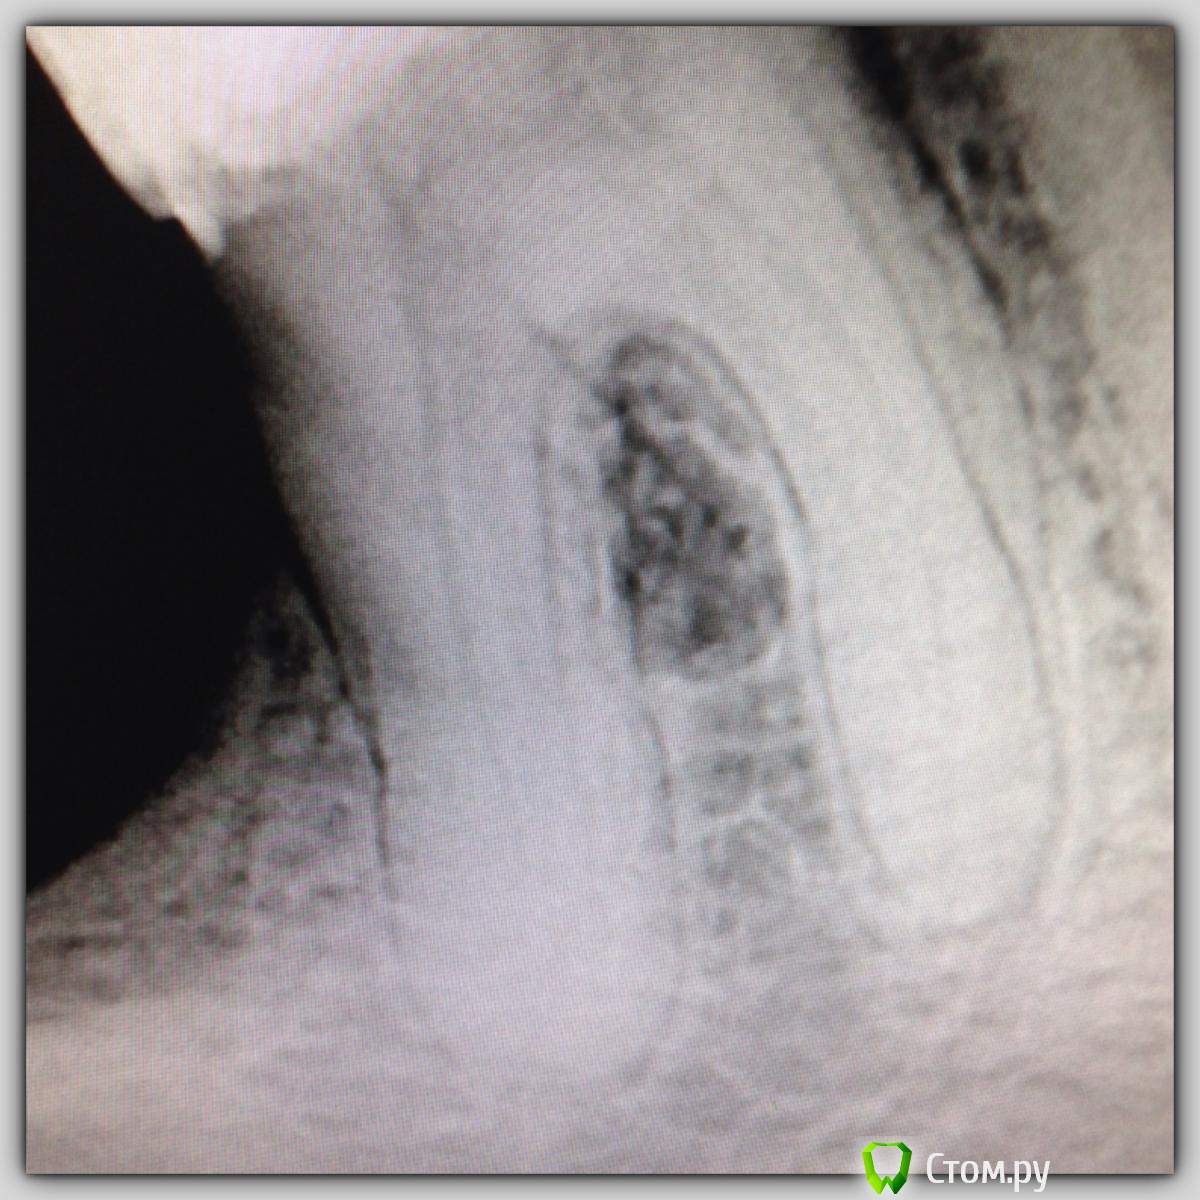

SSTi Опубликовано 15 октября, 2014 Автор Поделиться Опубликовано 15 октября, 2014 Продолжение истории сообщения 107. Прошло 5 месяцев. Пациент забежал сегодня записаться. Заодно сфоткались. Углы разные. И верхняя единица. Что думаете? 7 Ссылка на комментарий